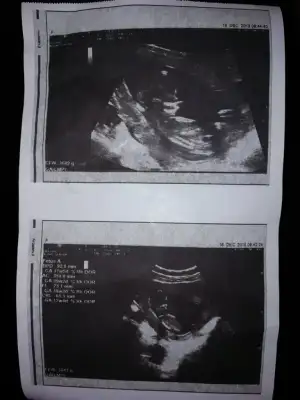

Buda 11 haftalık görüntüsü arkadaşlar. Tahmimde bulununnnn çatlicamm